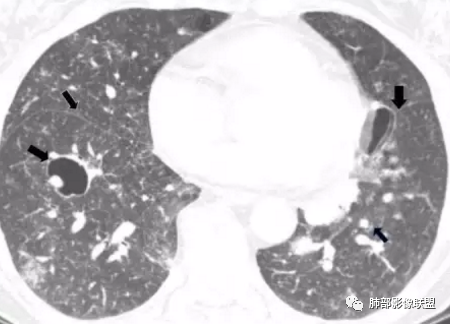

影像:双肺散在囊性病变,不规则,壁厚,部分见结节

晨读:女,31,间断咳嗽、咳痰9月。卵巢交界性囊腺瘤术后。胸部CT:双肺多发大小不等薄壁囊腔影,部分融合,形态不规则,个别囊壁偏厚。右肺上叶及左肺下叶纤维索条影。左下叶不规则囊腔影,壁不均匀增厚,周围不规则实性成分加GGO,放射性毛刺,胸膜牵拉。考虑:囊腔型Ca?转移?鉴别PLCH,Lam,LIp,BHD,CF,CPAM等,听大咖解析。

胸部CT:两肺多发囊腔,中上肺受累为主,囊腔形态不规则(囊有点丑),分叶状,囊壁厚薄不均,大部分囊壁薄。尚有一些结节影。

4.PLCH:常见于吸烟青年男性,囊腔形态不规则,呈分支状,囊壁厚薄不均,双侧肋膈角常不受累。

晨读囊不规则,分叶,存在PLCH可能,但为不吸烟女性,可能性下降。